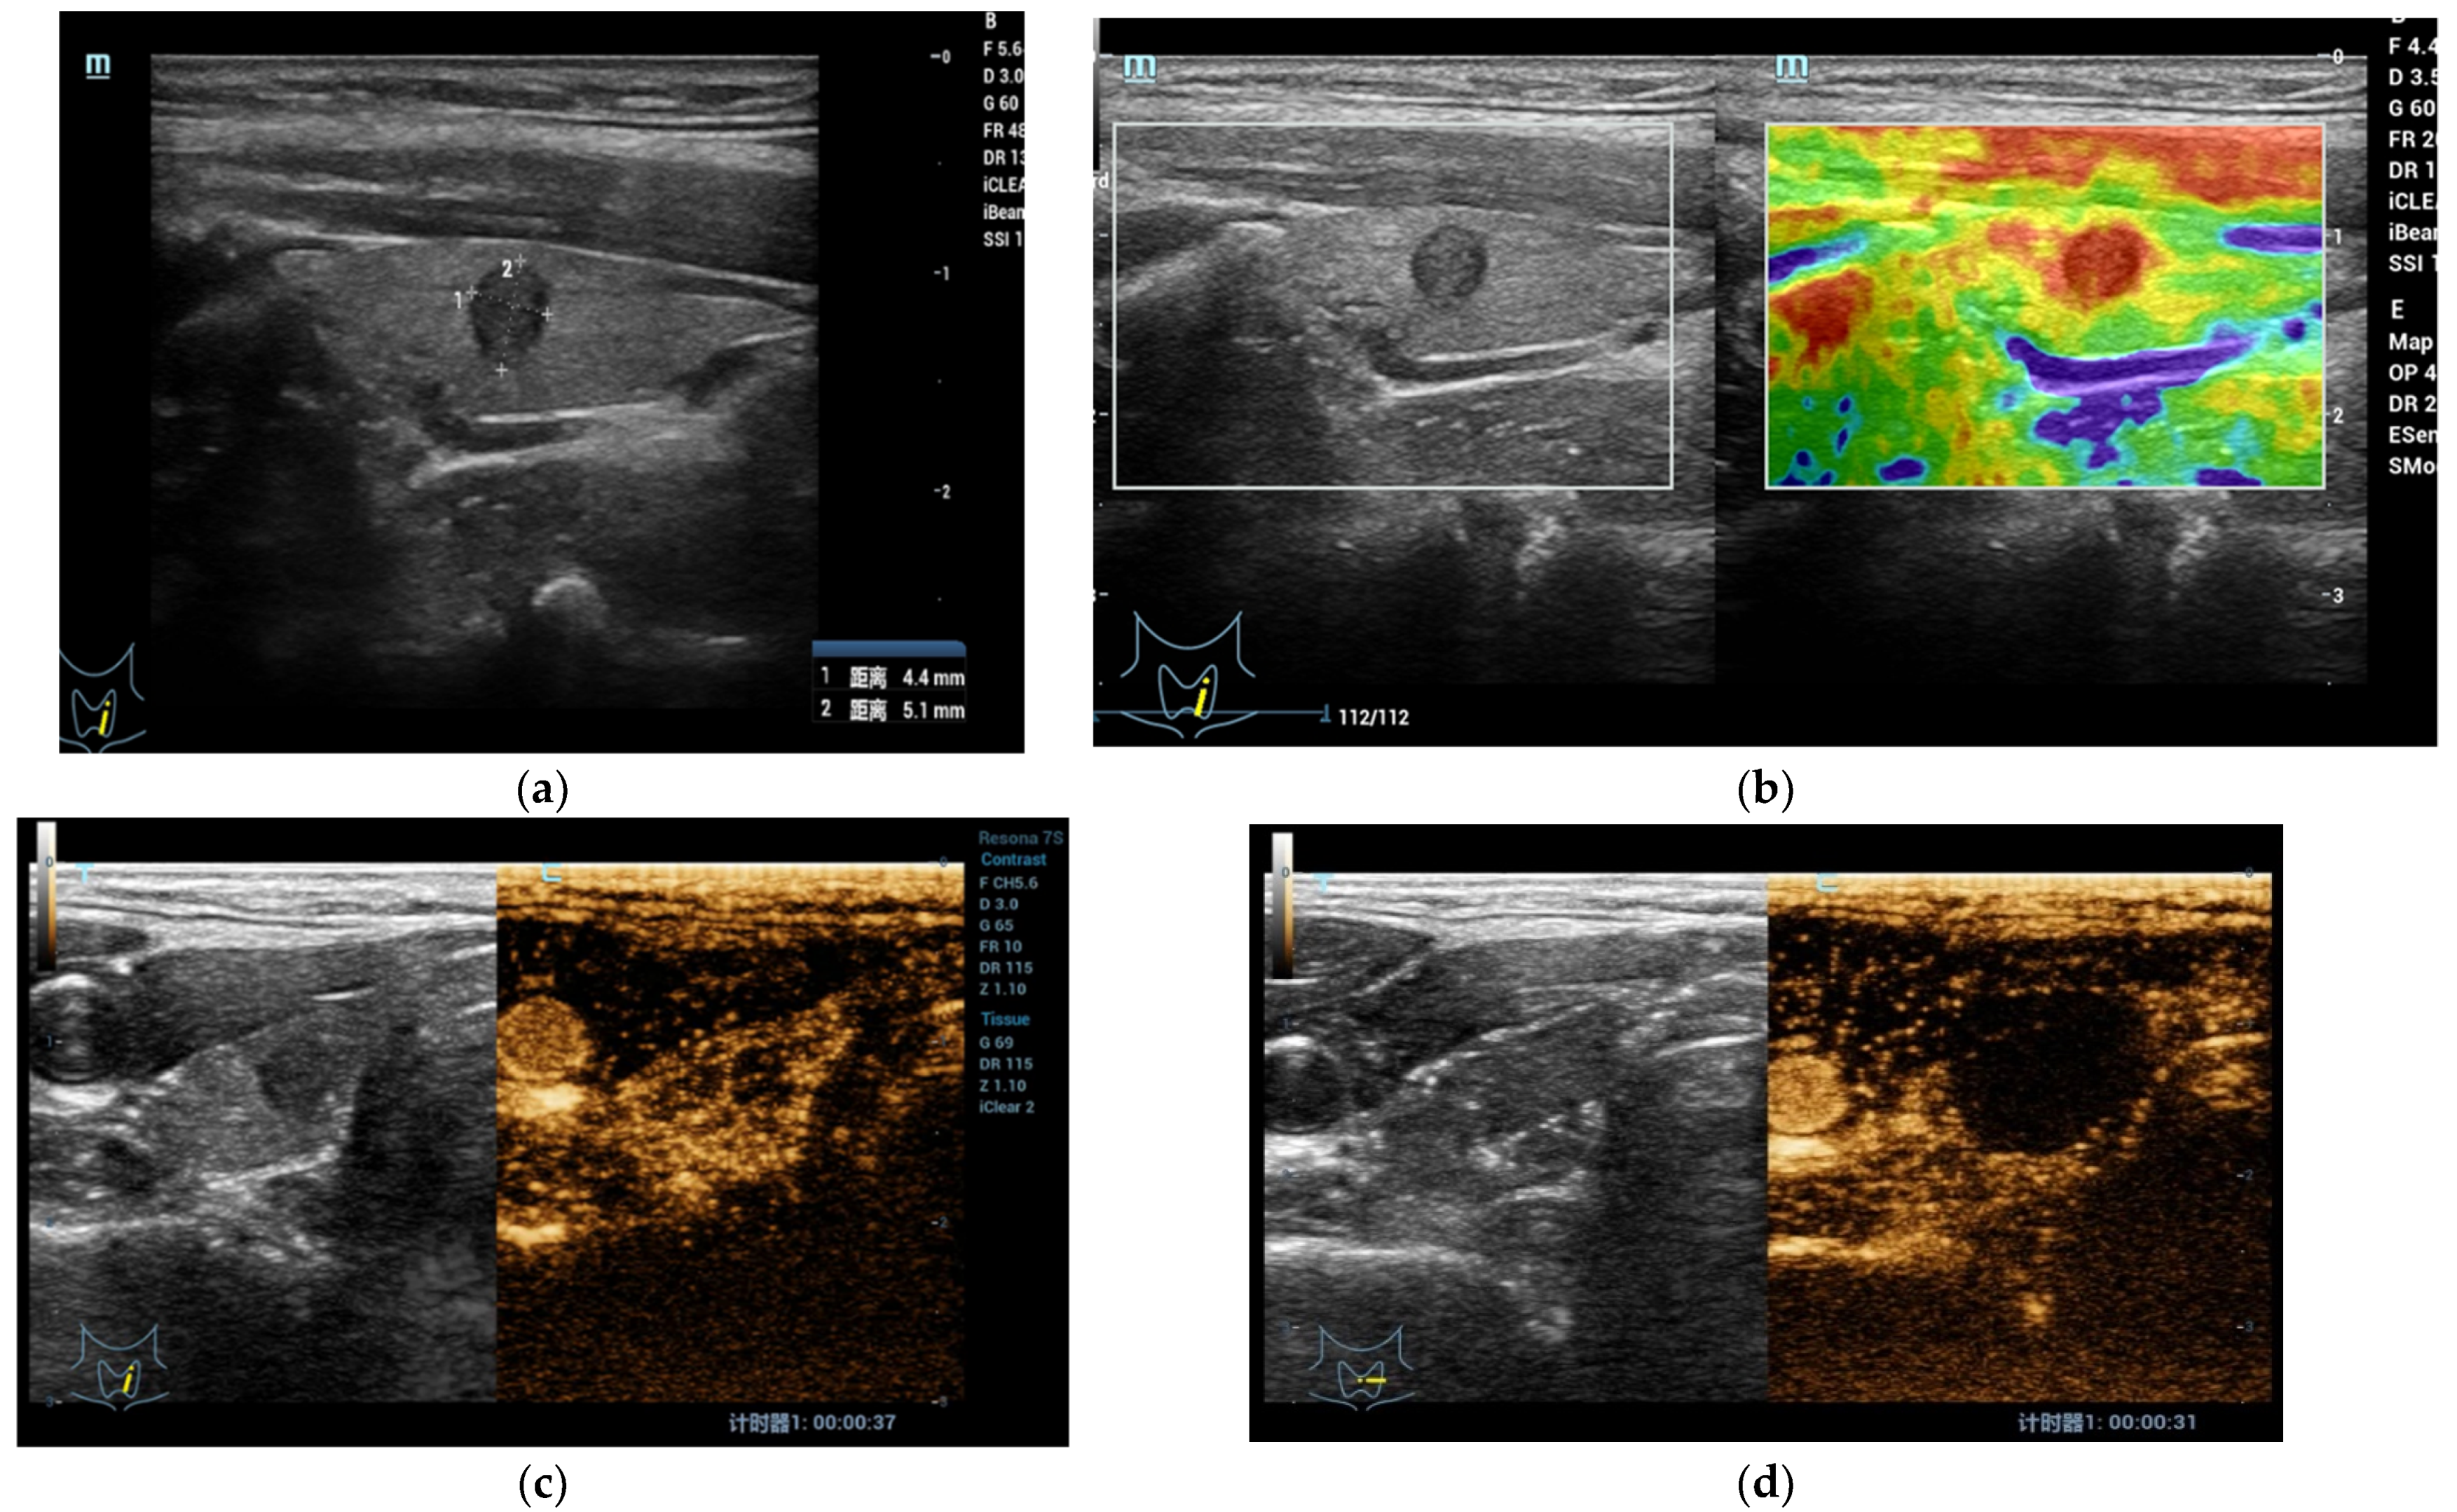

3.1. CEUS r in the Diagnosis of Thyroid Nodule

- Cantisani, V.; Consorti, F.; Guerrisi, A.; Guerrisi, I.; Ricci, P.; Di Segni, M.; Mancuso, E.; Scardella, L.; Milazzo, F.; D’Ambrosio, F.; et al. Prospective comparative evaluation of quantitative-elastosonography (Q-elastography) and contrast-enhanced ultrasound for the evaluation of thyroid nodules: Preliminary experience. Eur. J. Radiol. 2013, 82, 1892–1898. [Google Scholar] [CrossRef]

- Ma, S.; Zhou, P.; Wu, X.; Tian, S.; Zhao, Y. Detection of the Single-Session Complete Ablation Rate by Contrast-Enhanced Ultrasound during Ultrasound-Guided Laser Ablation for Benign Thyroid Nodules: A Prospective Study. Biomed Res. Int. 2016, 2016, 9565364. [Google Scholar] [CrossRef] [Green Version]

- Zhao, R.N.; Zhang, B.; Yang, X.; Jiang, Y.X.; Lai, X.J.; Zhang, X.Y. Logistic Regression Analysis of Contrast-Enhanced Ultrasound and Conventional Ultrasound Characteristics of Sub-centimeter Thyroid Nodules. Ultrasound Med. Biol. 2015, 41, 3102–3108. [Google Scholar] [CrossRef]